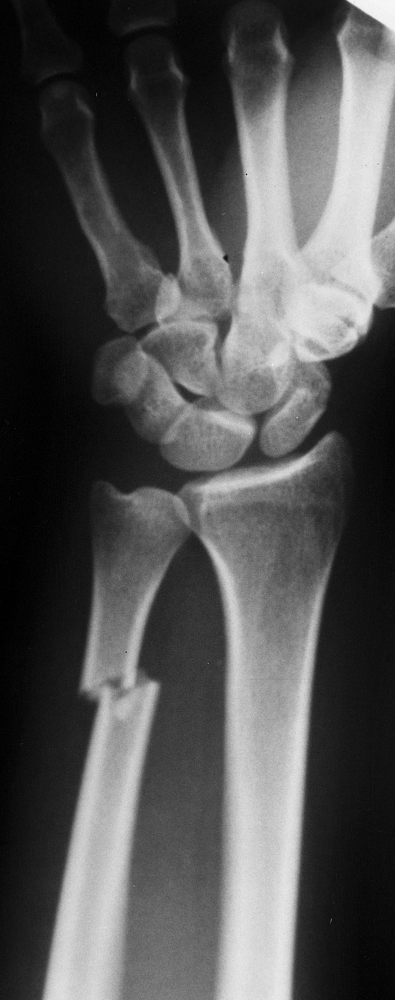

Closed transverse fracture of the distal third of the right ulna (Fig. 14.4).![]() Figure 14.4. Fracture of the right distal ulna. Figure 14.4. Fracture of the right distal ulna.